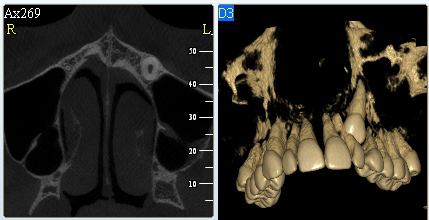

3D DVT - NewTom

Je speciální zubní digitální tříprostorový tomograf (3D), který umožňuje na základě jediného

snímkování vytvořit všechny typy RTG zobrazení, které jsou pro lékaře potřebné. Díky používané technologii tzv. „kuželového paprsku“ a speciálním senzorům je

výrazně zmenšená dávka záření - o více jak 80% proti klasickému CT vyšetření. To je významné zejména u dětí. Pomocí tohoto přístroje je možné zjisti skutečnou situaci v čelistních kostech pacienta tedy množství kosti - můžeme změřit skutečnou šířku i výšku kosti, i kvalitu kosti (hustotu) v místě uvažované implantace. 3D (tříprostorové) zobrazení umožňuje zvýšit prostorovou představu operatéra ještě před vlastní operací a zároveň pacientovi lépe objasnit a ukázat oblast plánovaného zavedení implantátu.

Pacient „neumí číst“ RTG snímky, ale díky 3D zobrazení vidí „svoji skutečnou čelist“

- např. jak je nízká či úzká, vidí průběh nervu nebo velikost čelistní dutiny, což mu umožní i pochopení nutnosti v některých případech provést pomocné zákroky ještě před vlastním zavedením implantátu (viz. kostní štěp, sinus lift, kostní granulát...).

Vyšetření pomocí tohoto přístroje používáme i ve stomatochirurgii (zlomeniny čelistí, zuby moudrosti, cysty, onemocnění čelistního kloubu), ortodoncii (retinované zuby, nadpočetné zuby), parodontologii atd.